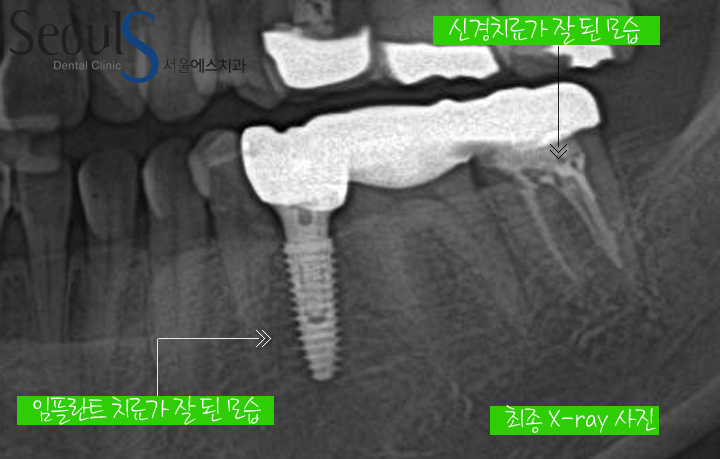

치료 후 X-ray 모습입니다

임플란트와 잇몸뼈가 단단히 잘 굳었고 신경치료도 잘 된 모습을 확인 할수 있습니다